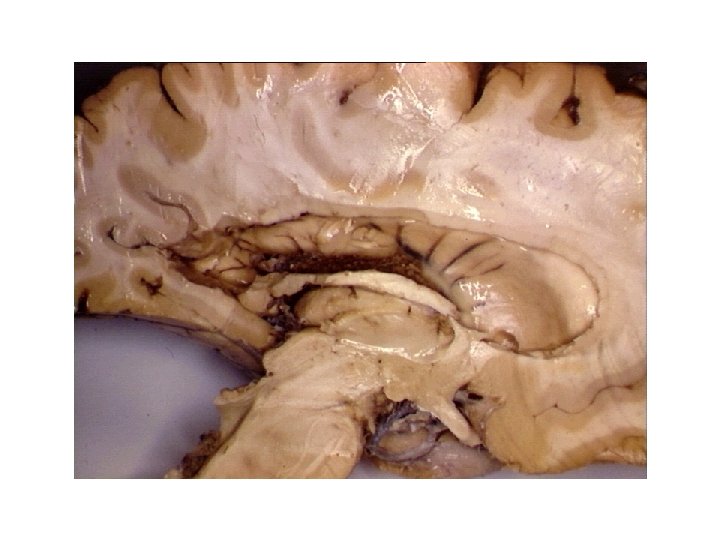

Limbic System: Limbic lobe + hippo. , fornix, MMBs, MTT, ant. nuc. thal. , cingulate cortex, cingulum, parahippo. gyrus then into hippo. stria terminalis? Papez circuit? Limbic Lobe